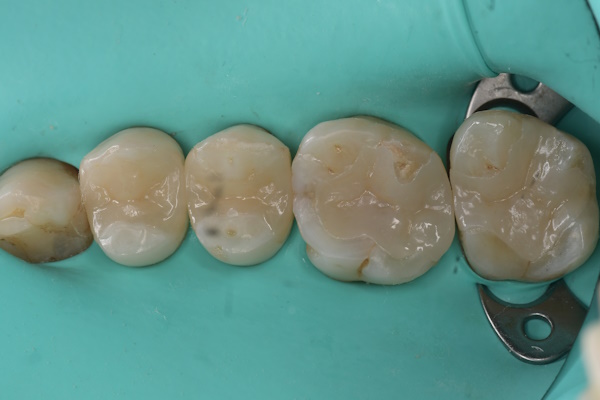

エッチング後(2回目)